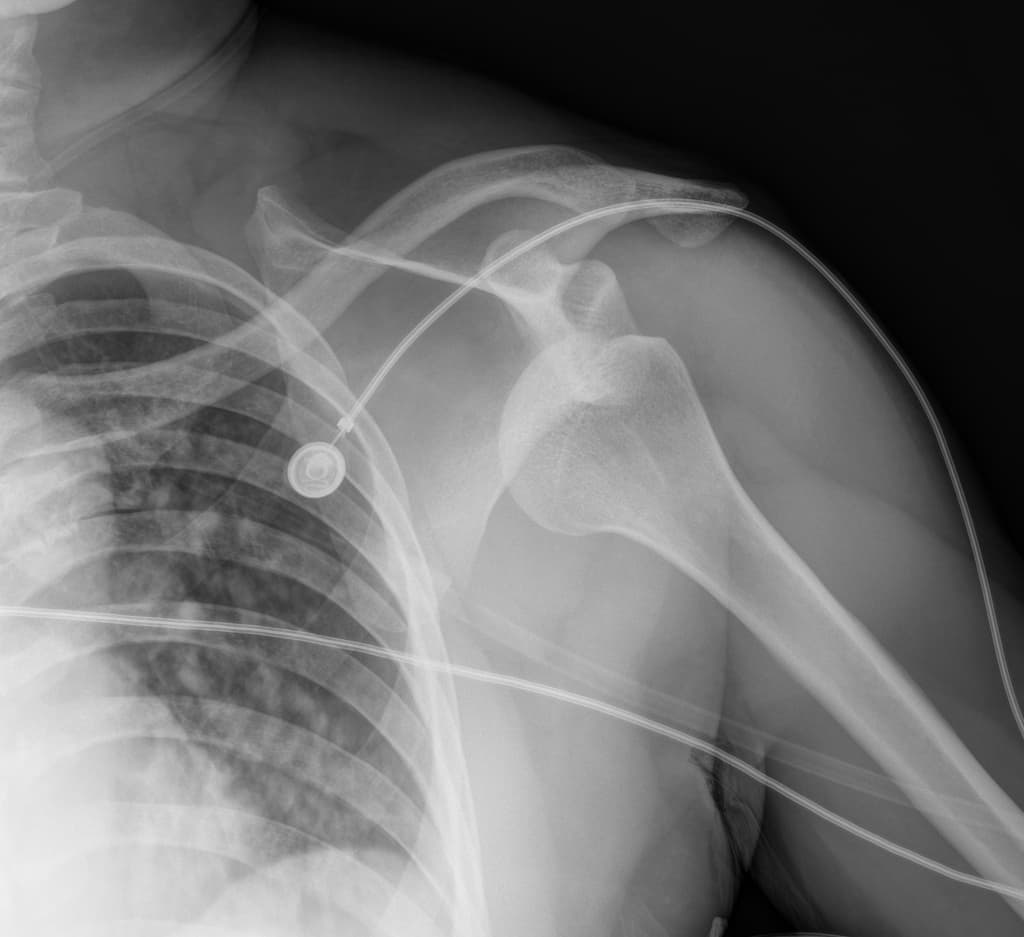

- Tràn khí màng phổi đỉnh bên phải mức độ nhẹ.

- Dịch màng phổi nhỏ bên phải, trong bối cảnh chấn thương, đây nhiều khả năng là tràn máu màng phổi (hemothorax).

- Không thấy rõ gãy xương sườn.

- Tràn khí màng phổi bên phải mức độ nhẹ và dịch màng phổi.